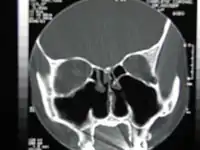

![]() CT scan of the nose after total bilateral turbinectomy/turbinoplasty | |